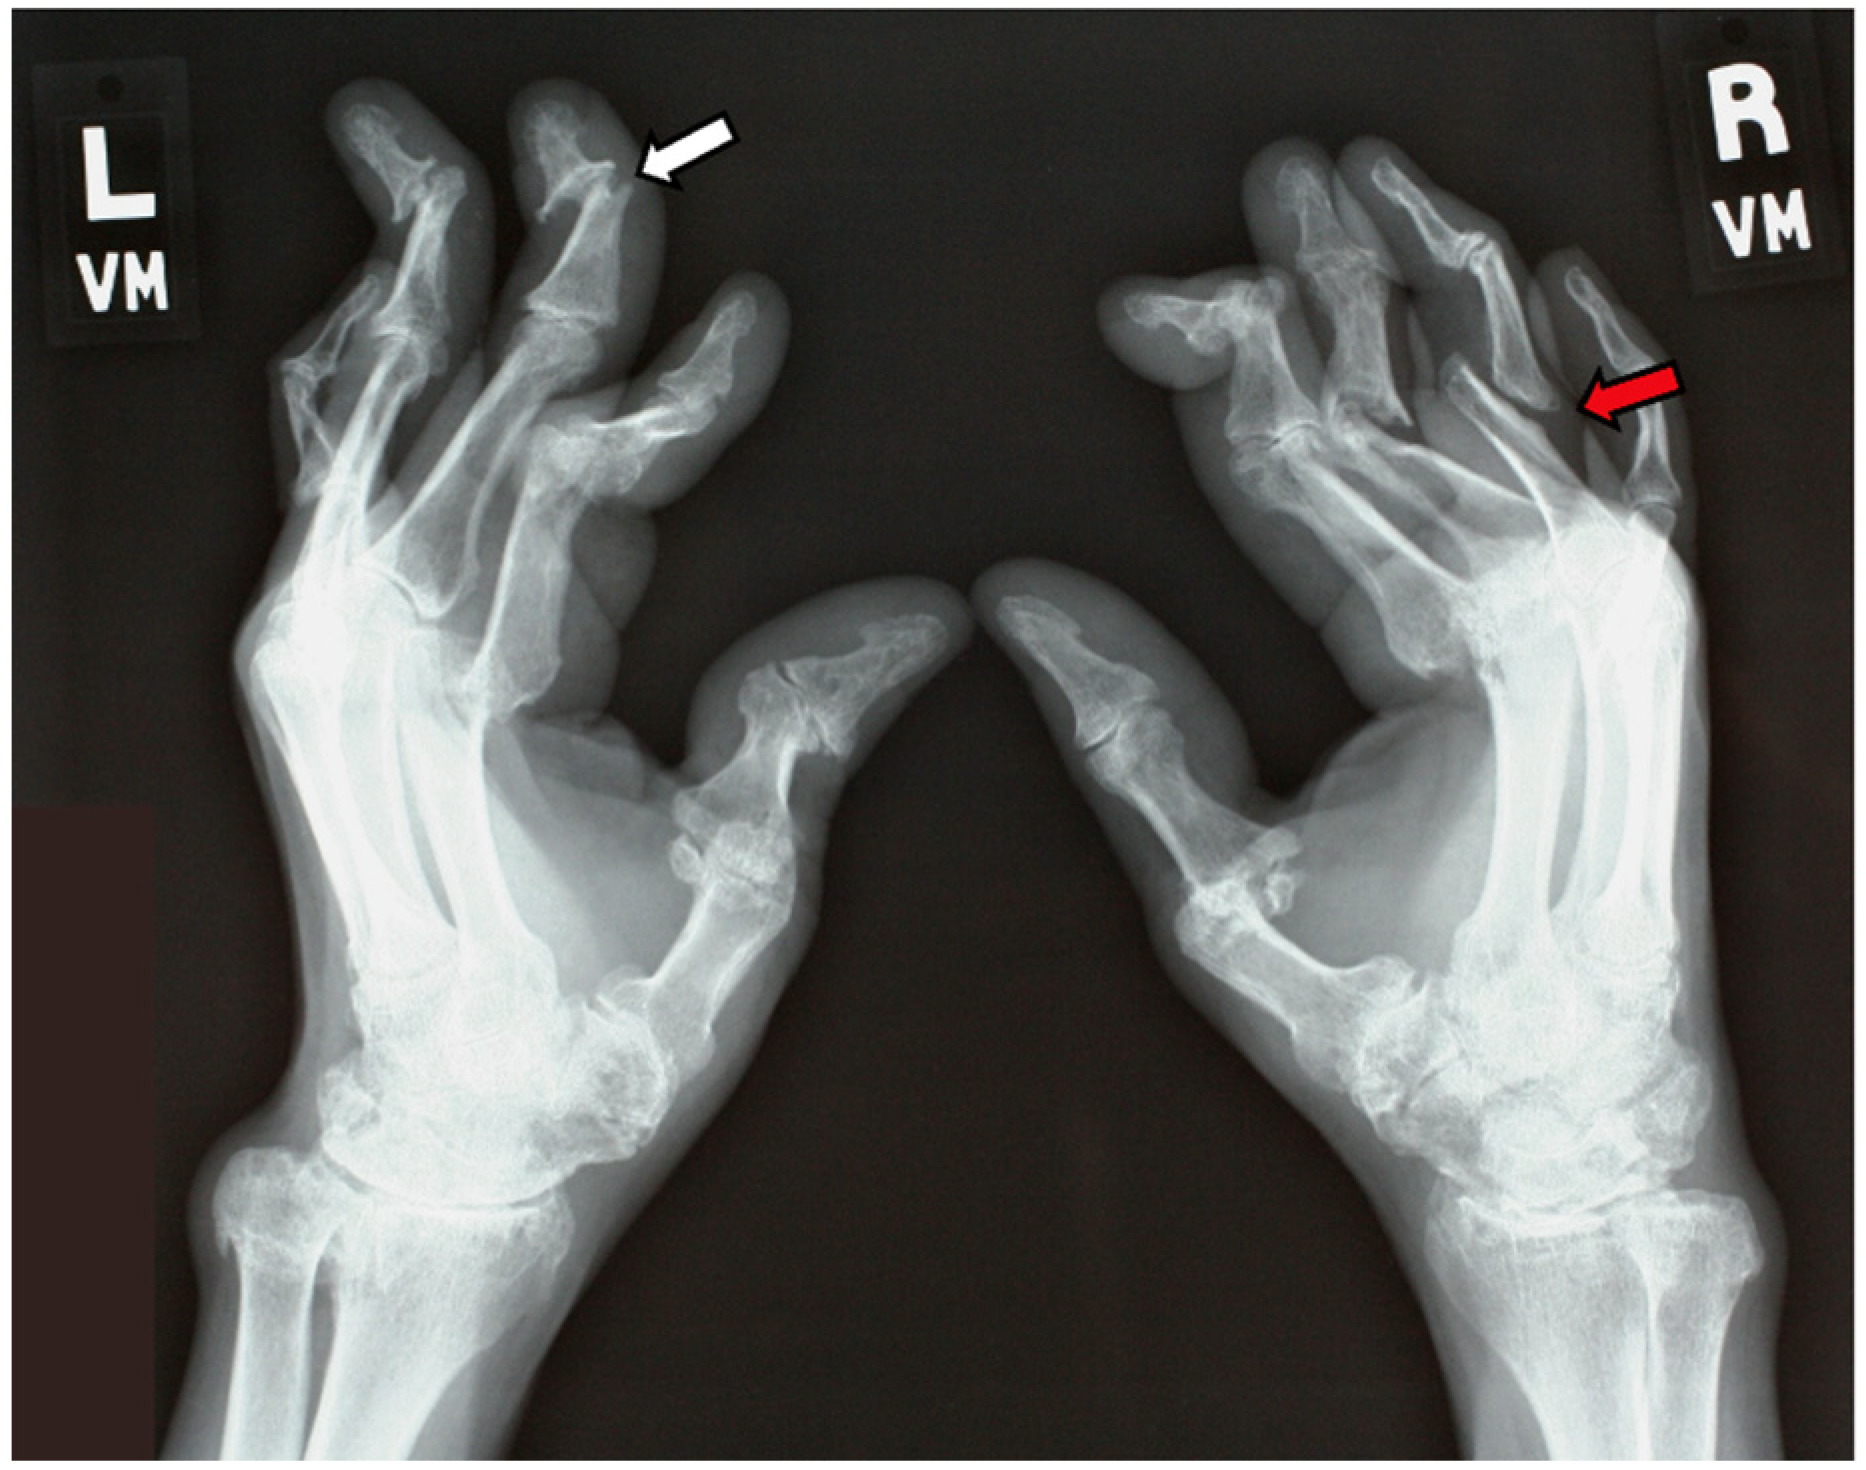

7.2.1. Plain Radiographs

- Haddad, A.; Johnson, S.R.; Somaily, M.; Fazelzad, R.; Kron, A.T.; Chau, C.; Chandran, V. Psoriatic Arthritis Mutilans: Clinical and Radiographic Criteria. A Systematic Review. J. Rheumatol. 2015, 42, 1432–1438. [Google Scholar] [CrossRef]